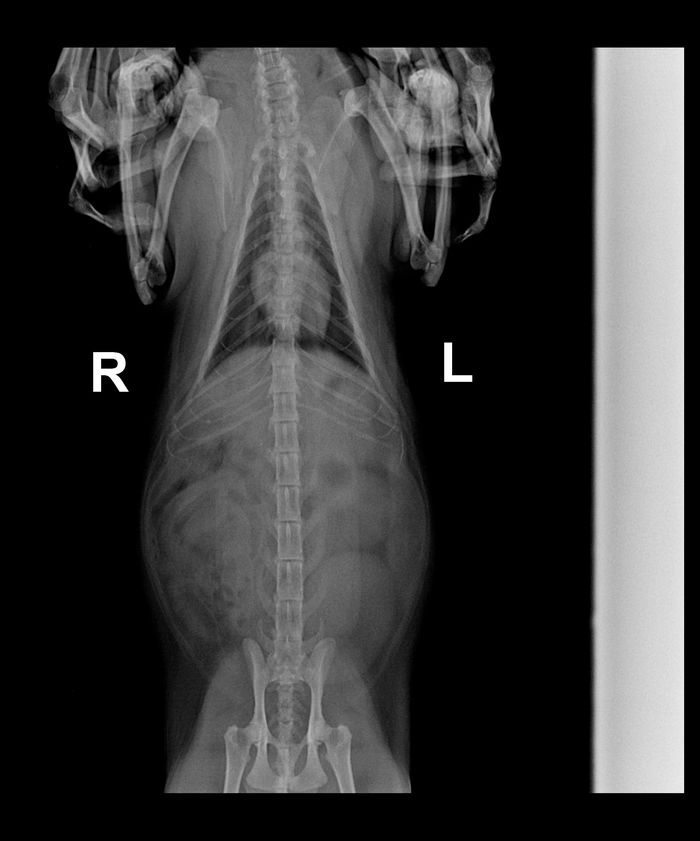

Рис. 10. Рентгеновгкие снимки скакательного сустава собаки (вверху) и кошки (внизу) в медио-лате-ральной (слева) и дорсо-плантар-ной (справа) проекции. Натуральная величина (снимки: проф. U. Matis) 1, 2 tibia: 1 corpus tibiae, 2 cochlea tibiae; 3, 4 fibula: 3 corpus fibulae, 4 malleolus lateralis; 5 — 7 calcaneus: 5 tuber calcanei, 6 processus coracoideus,

7 sustentaculum tali; 8—10 talus: 8 trochlea tali, 9 collum Cali, 10 corpus tali; 11 os tarsi centrale; 12 os tarsale primum; 13 os tarsale secundum; 14 os tarsale tertium, 15 os tarsale quartum; 16—20 ossa metatarsalia primum — quintum

Моей кошке 8 лет. Последние несколько месяцев страдает от того, что ей больно двигаться (сначала перестала запрыгивать на высокие поверхности, теперь вообще практически всегда лежит, встает только покушать и на лоток). Были у ветеринара, сделали рентген позвоночника. Нам сказали, что у кошки смещение позвонков и поможет только операция, а таких операций у нас в городе не делают.

Очень хотелось бы услышать мнение других специалистов, возможно ли медикаментозное лечение, и какие вообще отклонения они видят на рентгене?

Там же на снимке видно смещение 3 отделе , там где поясница .Я конечно не ветеринар ,я остеопат -массажист человеческий ,но смещение видно . И вопрос : есть ли слабость в задних лапах ,как ходит ? На полусогнутых или выпремляет лапы как обычно.И что со стулом .Как часто ходит на лоток. Если задние лапы ослабели ,есть понос и слабость мочевого ,однозначно есть протрузии поясничного отдела.

Перед кресцом L5-L6 позвонки ,не за что.Здоровья вам.

13-14 это грудной отдел ,там тоже есть.Но там именно просто смещение.А в поясничном похоже смещение на протрузии ,вот они дают ощутимую боль при движении и спрыгивании.Понимаете просто смещение болит конечно ,но не настолько сильно чтоб животное перестало залазить на возвышенность.

L4-5 и кристец пусть по смотрят ,она хвост поднимает и спрыгивает со стула к примеру?

Я не думаю ,я вижу что там есть смещение ,вопрос почему.Если симптомы совпадают с перечисленными ,то это протрузии ,или как их по другому называют грыжа межпозвоночная .И скорее всего это она и есть .Судя по тому что ухудшение наступало постепенно.Также болячка что у людей.